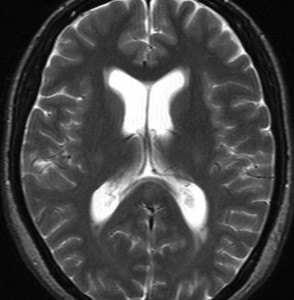

上矢状洞を埋め尽くすように増大して,頭蓋骨浸潤が著しい髄膜腫ですが,ごく軽度の右足脱力以外に何の症状もありません。上矢状洞はゆっくり閉塞すれば,このような頭頂部から後頭部にわたる広範閉塞でも,静脈還流に障害がない場合が多いといえます。大脳の前半部の血流は前頭葉表面の皮質静脈から海綿静脈洞に側副路を形成しています。頭蓋内圧亢進所見もなく,これらはこの髄膜腫がゆっくり増大したということを示唆しています。

手術直後の画像です。全部いっぺんに摘出するのは無理なので,まず前から80%くらいの腫瘍を摘出しました。肥厚した骨はチタンプレートで置き換えてあります。後頭部の上矢状洞内と大脳鎌に少し残りましたが,この6ヶ月後に2回目の開頭術をして全摘出しました。結果的にこの例では,上矢状洞を冠状縫合のあたりから,静脈洞交会まで壁ごと全部摘出しましたが,脳浮腫も何も生じませんでした。腫瘍の両側にある皮質静脈 cortical veinsを損傷しないことが肝要です。

右の病理像は,頭蓋骨浸潤している部分 ですが,骨破壊は良性髄膜腫に特徴的な骨内浸潤像です。この骨浸潤像は悪性像とはいえません。MIB-1は高いところで8%、低いところで3%程度です。